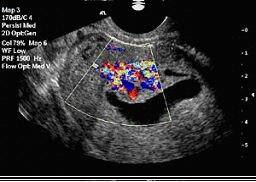

Сонохистерографията (хидротубация) е нова технология, показваща по-добре изображението на маточната кухина. При нея под ултразвуков контрол в маточната кухина се вкарва стерилен физиологичен разтвор с гъвкав и пластичен катетер, поставен в шийката на матката. Физиологичният разтвор разширява маточната кухина и осигурява отличен контраст с маточната лигавица, като с това подобрява визуализацията на маточната и ендометриална патология. Тази технология може също така да се използва за оценка на маточните тръби чрез изливане на флуид към таза. Цветното доплерово изображение показва движението на ултразвуковите вълни през контрастната среда вътре в тръбите. С хидротубацията се проверява и проходимостта на маточните тръби – това е безболезнена процедура под ултразвуков контрол, след която често пъти може спонтанно да настъпи бременност поради реканализация на малки сраствания

Цветно доплерово изображение на маточни полипи, наблюдвана при сонохистерография. |

Инжектирането на солеви разтвор в маточната кухина раздалечава двете страни на ендометриума и подобрява визуализацията на някои структури, като напр. полипите. В допълнение, солевият разтвор служи за контрастно вещество, което позволява да се видят вътрематочни сраствания (синехии).